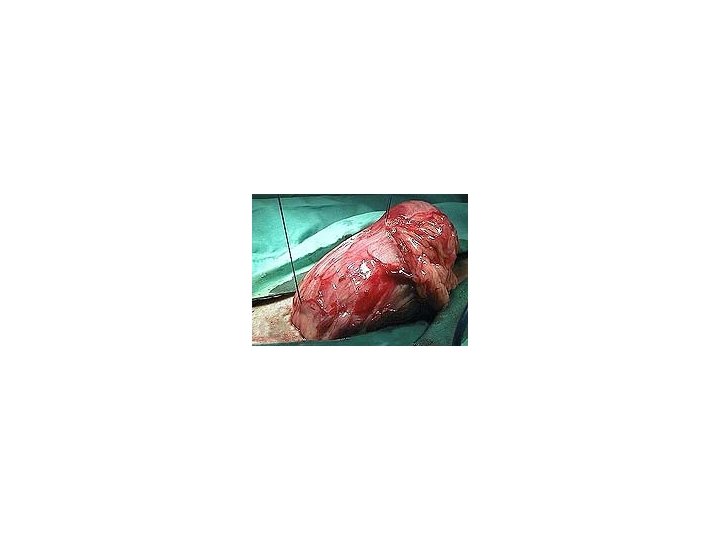

Calcium oxalate stones can not be dissolved by diet and must be surgically removed. 50% of animals who undergo cystotomy sx will redevelop stones within 3 years.

Cystotomy :